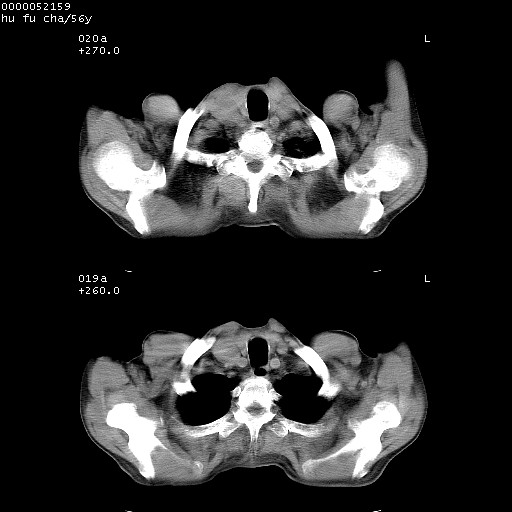

以下是引用zsl6918在2008-8-25 22:47:00的发言:[br]胸骨,胸椎及肋骨均可见多发转移表现,肝内低密度结节不除外转移。原发灶可能在右肺。双侧可见支扩表现。

以下是引用卜一在2008-8-26 8:02:00的发言:[br][br] 支持:肺癌并肺内,胸骨,胁骨,胸椎及肝内转移!另:左肺支气管扩张征伴感染! [br]

以下是引用zjzjr在2008-8-26 11:03:00的发言:[br]支持:肺癌并肺内,胸骨,胁骨,胸椎及肝内转移!另:左肺支气管扩张征伴感染!